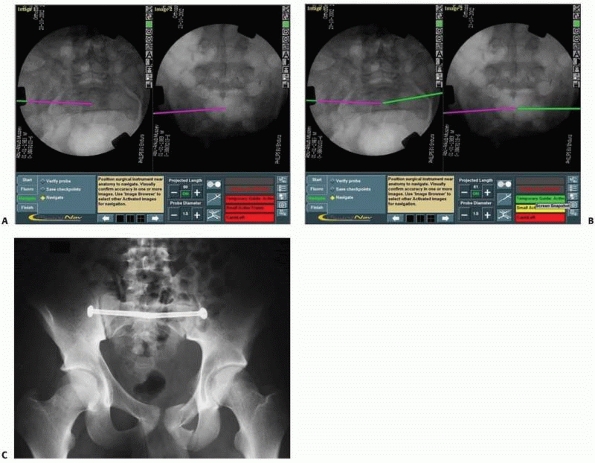

in the fixation of fractures or dislocations in the sacroiliac zone,

the acquired fluoroscopic views can be used for the insertion of more

than one screw (Figs. 17-13 and 17-14).

FIGURE 17-13 Bilateral sacroiliac screws. A,B.

Typical intraoperative display of computer screen during bilateral insertion of two sacroiliac screws. The live spatial position of the drill guide is simultaneously presented on two views (inlet and outlet) with a virtual continuation representing the track of the guidewire. C. Postoperative verification radiograph showing the accurate real position of the two sacroiliac screws after the navigation process. (Images property of authors.) |